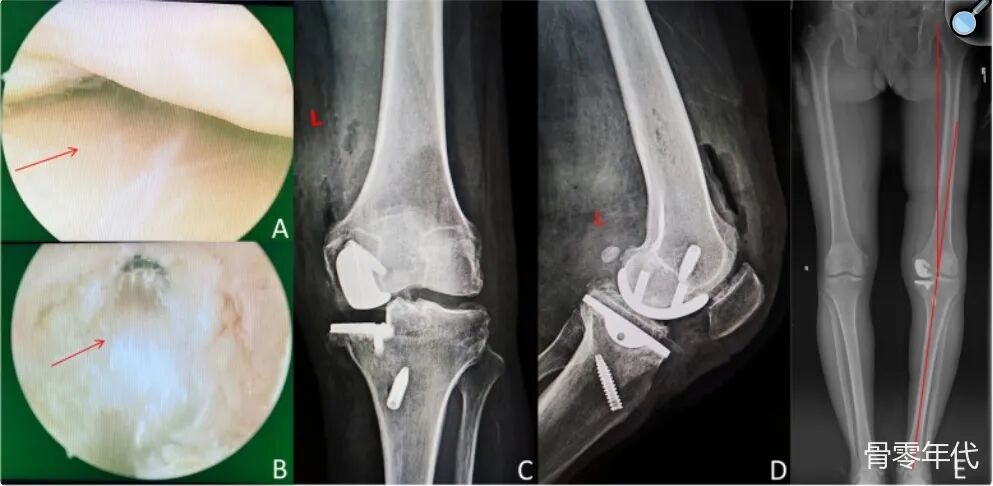

影像学表现